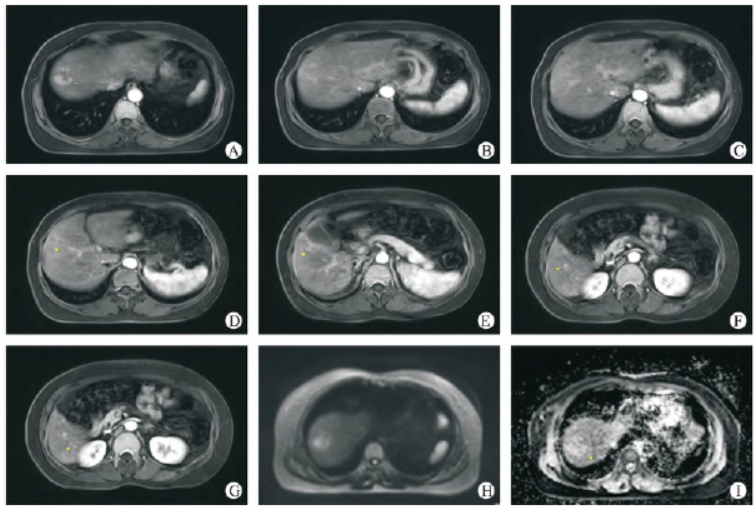

患者女性,53 岁,在体检时发现肝内多发结节(约14个),较大者位于肝右叶S8 段,大小约4.2 cm × 5.2 cm ×2.9 cm,多考虑肝癌;肝左叶囊肿(图1)。肿瘤标志物示:AFP 415 IU/mL。行超声引导下肝脏肿物穿刺活检术,穿刺病检示:(肝肿物穿刺活检组织)肝细胞癌,中分化(图2)。

图1 治疗前肝脏多发HCCA - G:在CIRT(2022 - 12 - 02)之前MRI T1增强的不同层面示肝内多发异常强化结节肿块(共14 个),较大者位于肝S8 段,大小约4.2 cm ×5.2 cm × 2.9 cm;H - I:DWI 示弥散受限,ADC 值1.066 mm3 /s。